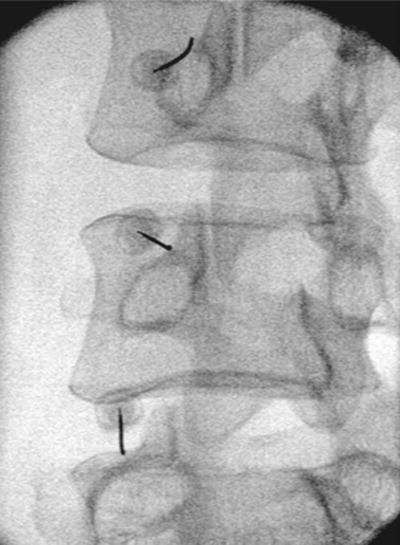

Στην διατρηματική έγχυση, υπό ακτινοσκοπική καθοδήγηση, το φαρμακευτικό διάλυμα χορηγείται απευθείας στο σημείο εξόδου της νευρικής ρίζας, για την αντιμετώπιση του ριζιτικού άλγους.

Πρόκειται για μια ελάχιστα επεμβατική πράξη, όπου μια ειδική βελόνα με ενσωματωμένο ηλεκτρόδιο εισάγεται στο σπονδυλικό τρήμα στο επίπεδο του ραχιαίου γαγγλίου της οπίσθιας ρίζας. με χρήση παλμικής ραδιοσυχνότητας γίνεται η διέγερση του γαγγλίου, με στόχο την τροποποίηση της μεταφοράς και αντίληψης των επώδυνων μηνυμάτων.